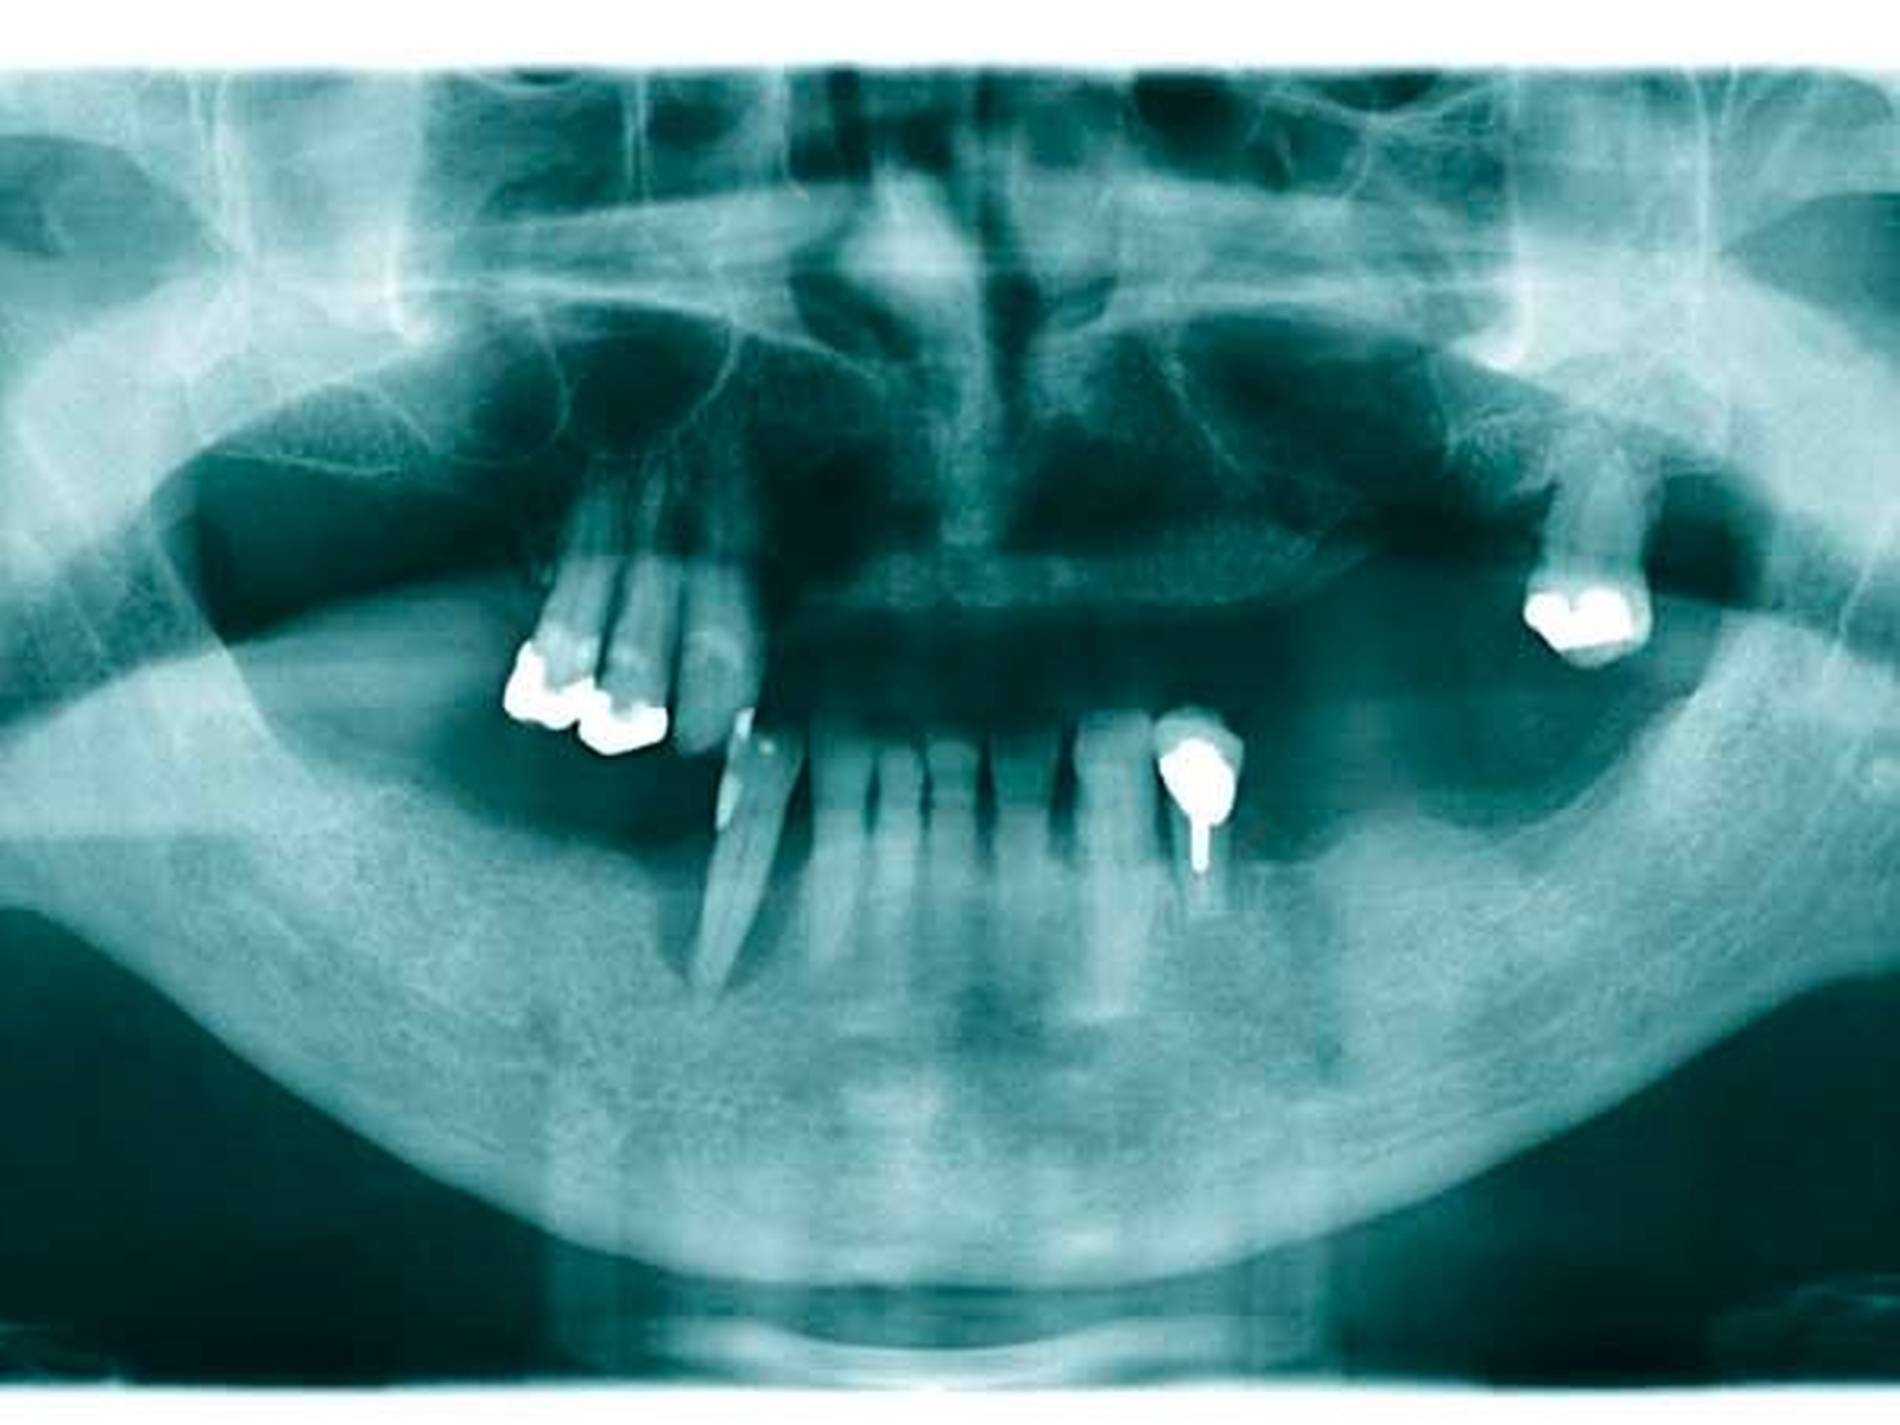

Patientenfall 4

Das Orthopantomogramm (Abbildung 17) zeigt die Gebisssituation einer 49-jährigen Patientin nach Abschluss einer parodontalen Vorbehandlung. Die sehr gepflegte Patientin betreibt eine intensive Mundhygiene, legt hohen Wert auf ihre äußere Erscheinung. Ihre finanzielle Limitation lässt aber keine implantatprothetische oder aufwendige kombiniert festsitzend-herausnehmbare Versorgung zu. Da die Patientin eine hohe Lachlinie hat und eine Demaskierung durch sichtbare Gussklammern im Bereich der Frontzähne fürchtete (Abbildung 18), verweigerte sie konventionellen gussklammerverankerten Zahnersatz und trug entgegen ausdrücklichem zahnärztlichem Rat dauerhaft eine rein schleimhautgelagerte Teilprothese. Die Patientin wurde mit der Bitte um Beratung und Behandlungsübernahme an unsere Einrichtung überwiesen.

Diese Patientin konnte an unserer Einrichtung mit der Modifikation eines gussklammerverankerten Zahnersatzes versorgt werden, bei dem die anterioren sichtbaren Klammer-Retentionsarme aus dem gingivafarbenen Kunststoff Polyamid-12 (Valplast) angefertigt wurden (Abbildungen 19 und 20). Die Polyamidretentionarme müssen aufgrund des wesentlich geringeren Elastizitätsmoduls gegenüber einer CoCrMo-Legierung wesentlich breiter gestaltet werden. Sie liegen allerdings nur den vestibulären Flächen der Ankerzähne an und sind unter der partiell mitbedeckten Gingiva hohlgelegt (Abbildung 21).